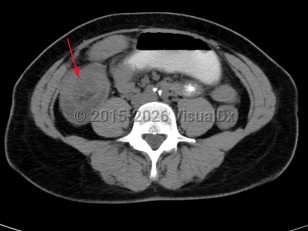

Intussusception is a telescoping or invagination of a part of the intestine into the lumen of an adjacent segment. Intussusception can present with variable severity. It can present with bowel ischemia and perforation with need for emergent surgical intervention, or it can present as relaxing / remitting abdominal pain of unclear etiology with intermittent symptoms and no signs of systemic illness. Jejunojejunal, jejunoileal, ileoileal, ileocolonic, and colocolonic are all types of intussusception that can occur, with the majority involving the small intestine.

Intussusception occurs in children and adults. It is the most common cause of bowel obstruction in children, where it presents with sudden onset of acute abdominal pain and inconsolability, and at times with emesis, a palpable abdominal mass, or hematochezia. Tucking knees into the torso is consoling in some instances. In pediatrics, intussusception is most commonly due to viral illnesses, with mesenteric lymphadenopathy creating a lead point to trigger intussusception. Tumors, polyps, Meckel diverticulum, or postsurgical adhesions are additional causes that can trigger intussusception.

Intussusception in adults presents with similar symptoms: sudden-onset abdominal pain that can relax and remit, with or without symptoms of acute bowel obstruction and hematochezia. Intussusception in adults can also be caused by viral infections, polyps, or postsurgical adhesions, but there is greater concern for underlying malignancy – either small or large bowel or extrinsic (eg, lymphoma) – as a trigger point.

In both adults and children, prolonged intussusception can cause bowel ischemia, resulting in hematochezia due to mucosal sloughing and a risk of bowel perforation. Concern for intussusception should prompt emergent medical evaluation at a hospital with radiology, gastroenterology, and general surgery available on call.